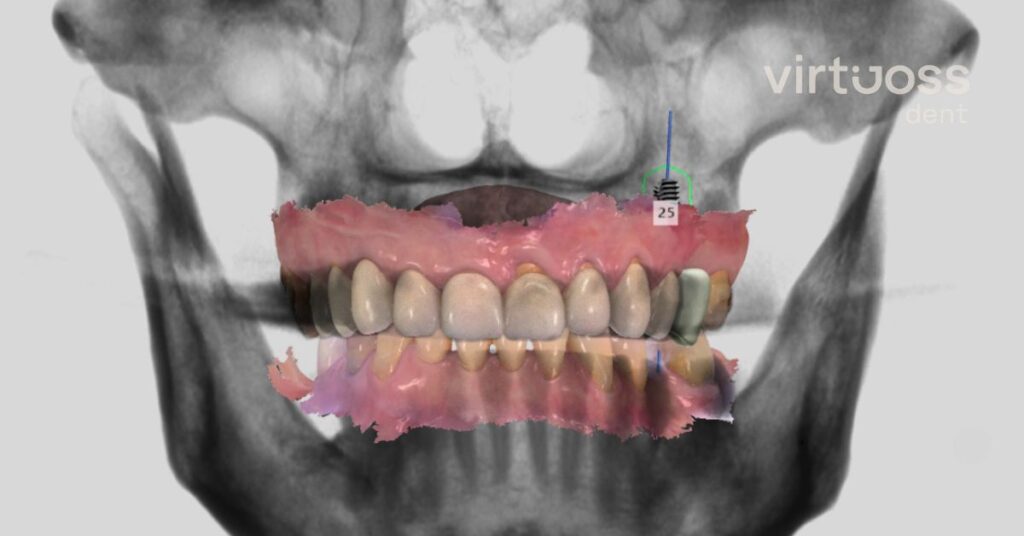

Výše zmíněné 3D rentgeny (CT skeny) jsou navíc zásadní pro plánování implantátů. Díky těmto informacím vytvoříme léčebné plány a zubní náhrady, které vám budou sloužit roky.

4. Digitální design úsměvu – společně naplánujeme nový úsměv

V zubní ordinaci Virtuoss dent používáme technologie, které nám umožní efektivně prodiskutovat vaše možnosti. Zohledníme vaše nároky, očekávání a dokonce nahlédneme, jak by vaše nové zuby mohly vypadat. V některých případech si nový úsměv budete moci v ordinaci i vyzkoušet.